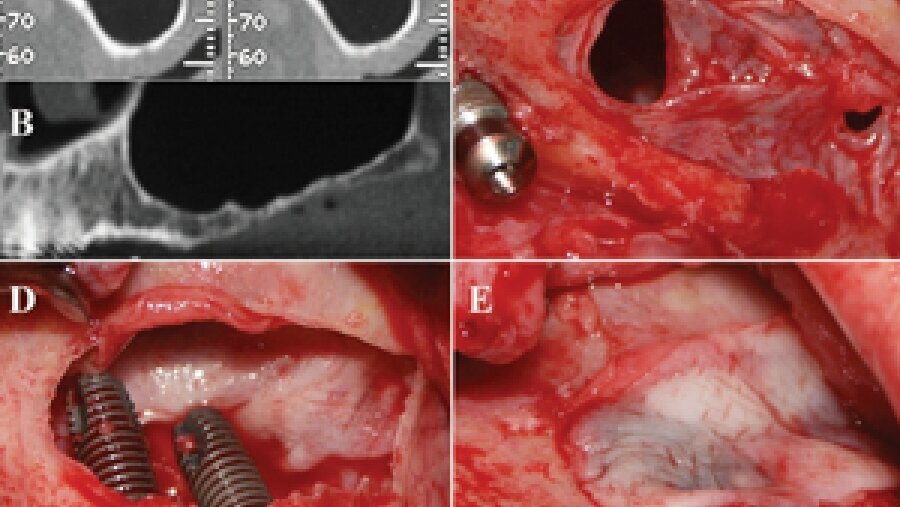

Figs. 10a-e: PRF is used in invasive surgery.

PRF is used in invasive osseous surgery close to the eyes, ear, brain and in direct contact with bone, maxillary sinus, veins, arteries and nerves that could be adversely affected, if proper contamination control protocols are not followed.